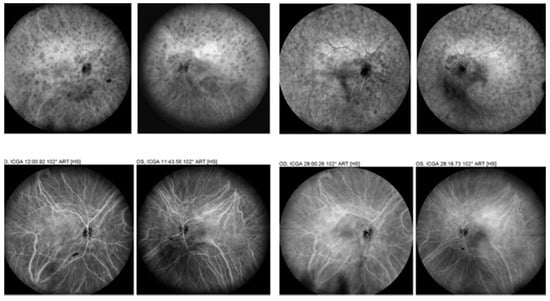

- Tian, M.; Zeng, G.; Tappeiner, C.; Zinkernagel, M.S.; Wolf, S.; Munk, M.R. Comparison of Indocyanine Green Angiography and Swept-Source Wide-Field Optical Coherence Tomography Angiography in Posterior Uveitis. Front. Med. 2022, 9, 853315. [Google Scholar] [CrossRef] [PubMed]